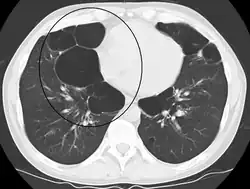

Advanced centrilobular emphysema showing total lobule involvement on the left side

Centrilobular emphysema, also called centriacinar emphysema, affects the centre of a pulmonary lobule (centrilobular) in the lung, the area around the terminal bronchiole and the first respiratory bronchiole, and can be seen on imaging as an area around the tip of the visible pulmonary artery. Centrilobular emphysema is the most common type usually associated with smoking, and with chronic bronchitis.[17] The disease progresses from the centrilobular portion, leaving the lung parenchyma in the surrounding (perilobular) region preserved.[23] Usually the upper lobes of the lungs are affected.[17] The upper lobes of the lungs are more susceptible to centrilobular emphysema because of their higher ventilation:perfusion ratio due to gravity. The apices of the lungs have less particle filtration because of lower blood and lymphatic flow compared to the bases of the lungs.[24][25]